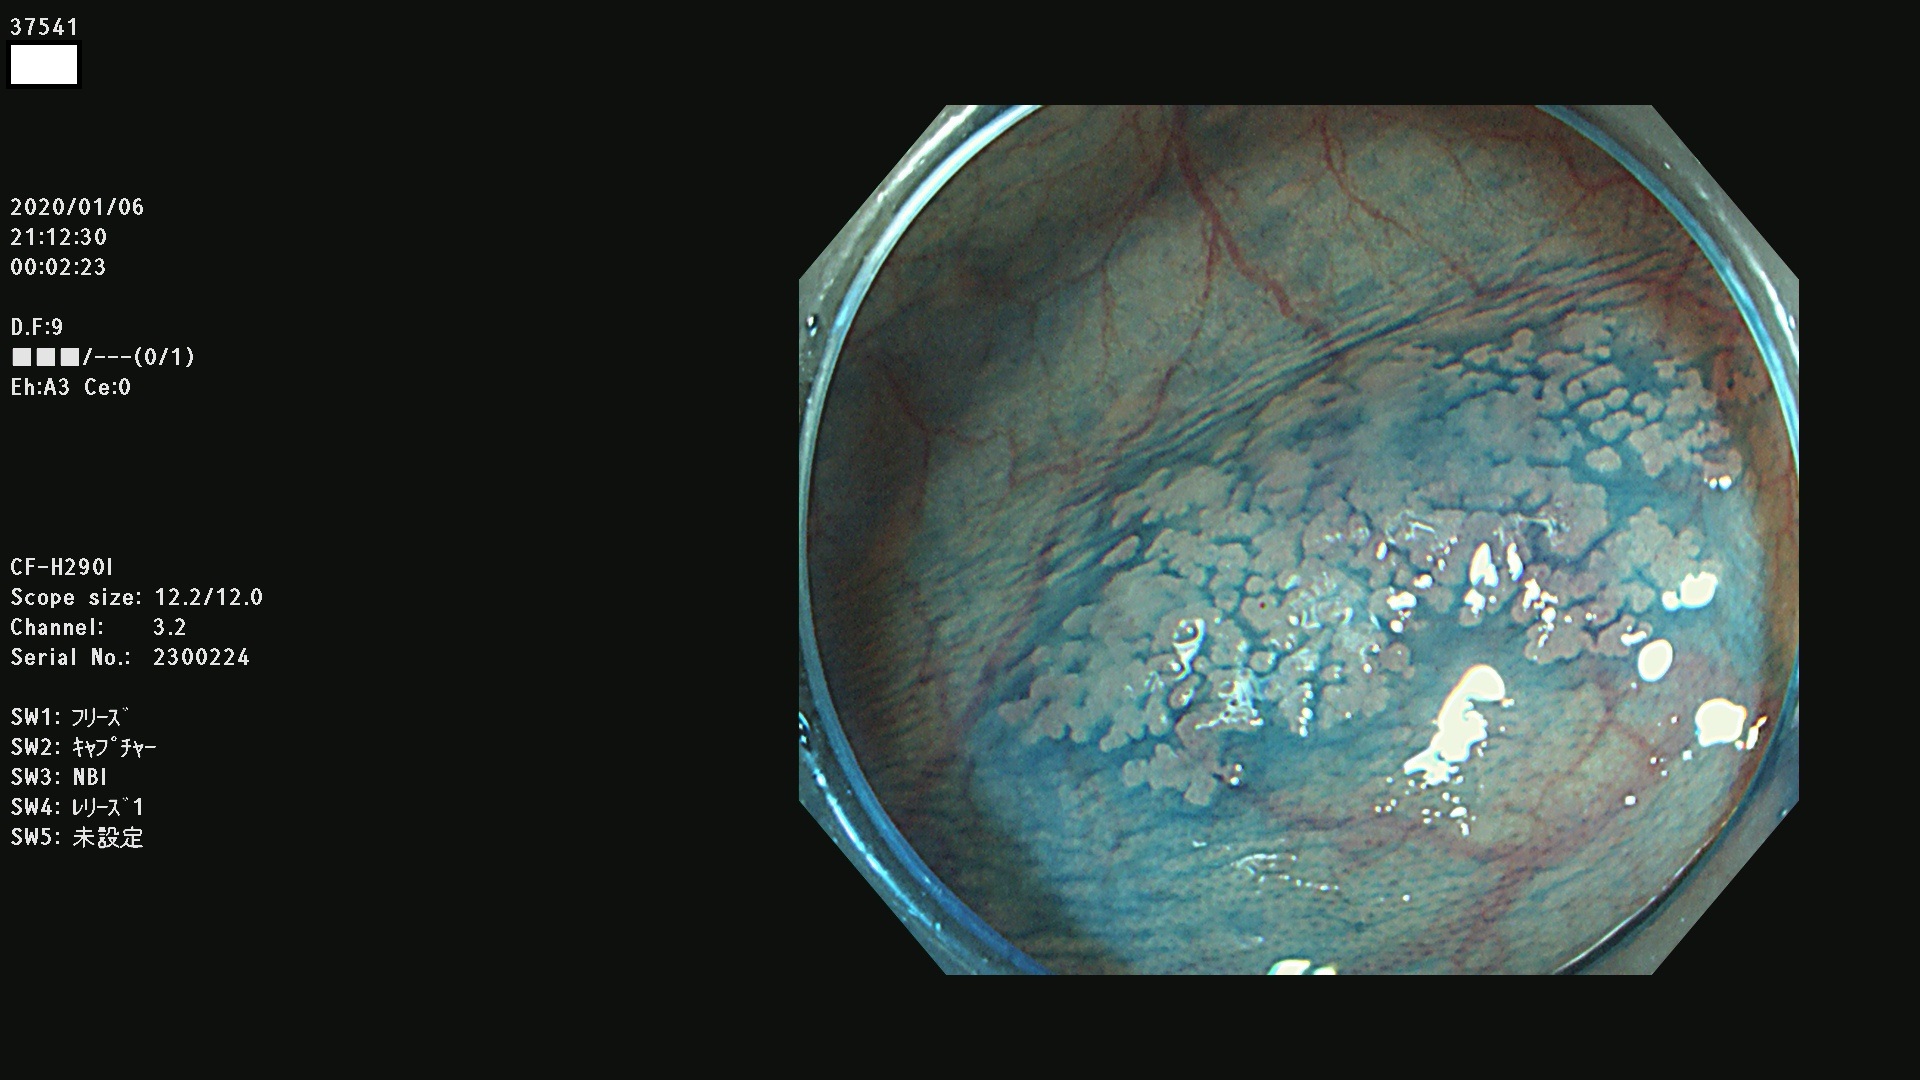

発見困難で危険性の高い平坦型病変(上記100名より抽出) ![]()